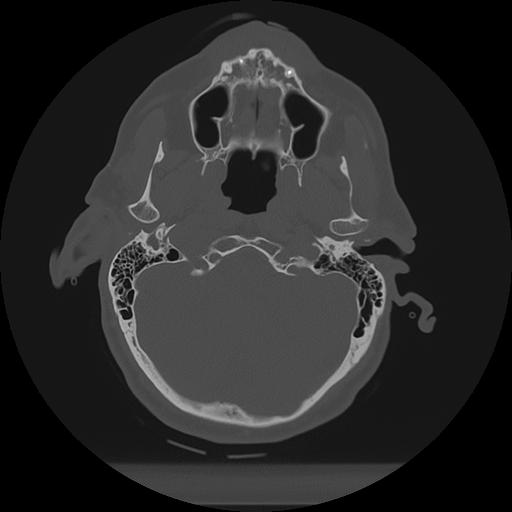

11 HUESO,,Axial,2.0,HUESO,,